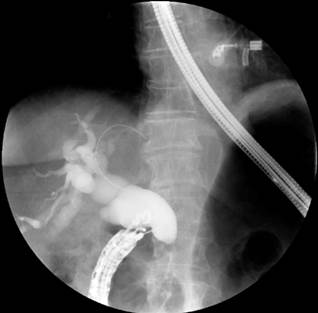

Based on these findings, palliative care was decided by performing a biliary stent placement by means of an ERCP. During the procedure, the papilla was found to be distorted with local retraction of the duodenal walls, and despite cannulation of the distal bile duct was achieved, cannulation of the proximal bile duct was unsuccessful. EUS-guided biliodigestive shunt was then performed, in which a neoplastic infiltration of the duodenal papilla preventing its cannulation and a 23 mm heterogeneous hypoechoic lesion in the head of the pancreas with an up to 18 mm retrograde bile duct dilation were found (Figure 4). An initial puncture of the mass was performed for histological study purposes and then of the transduodenal bile duct with a 19 Fr. needle, which allowed the advancement of the 0.035” hydrophilic guide wire; dilatation was achieved using a biliary balloon dilator under fluoroscopic control and subsequent placement of the 10 x 80 mm fully covered metal stent was performed, which was released under endoscopic and fluoroscopic control achieving adequate opening and drainage of the contrast medium and clear bile, without subsequent complications (Figures 5 and 6). The cytology report of the samples obtained through endosonography confirmed adenocarcinoma involvement. Two months later, a total bilirubin control was performed obtaining the following results: total bilirubin: 2.42 mg/dL; direct bilirubin: 1.85 mg/dL, and indirect bilirubin: 0.58 mg/dL (Figure 7). Palliative care was continued in the oncology service.

Figure 5 Endoscopic-guided bile duct cannulation and fluoroscopy in which dilatation with distal amputation is observed.